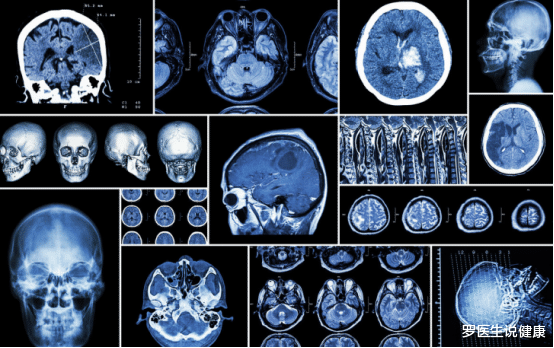

丽丽被送往医院后 , 医生发现脑部血管大面积堵塞 , 最终经过了3个小时的抢救 , 还是没能挺过去 , 离开了人世 , 医生感叹:唉 , 身体早有提醒 , 是她自己没在意啊!”

血脂升高身体会出现以下几种情况 , 不可忽视 , 避免恶化脑梗

l头晕头痛 , 精神不振 。

l四肢出现麻木感 。

l舌体发硬 , 经常流口水 。

l走路喜欢一边倾斜 。

l思维缓慢 , 头脑不清晰 。